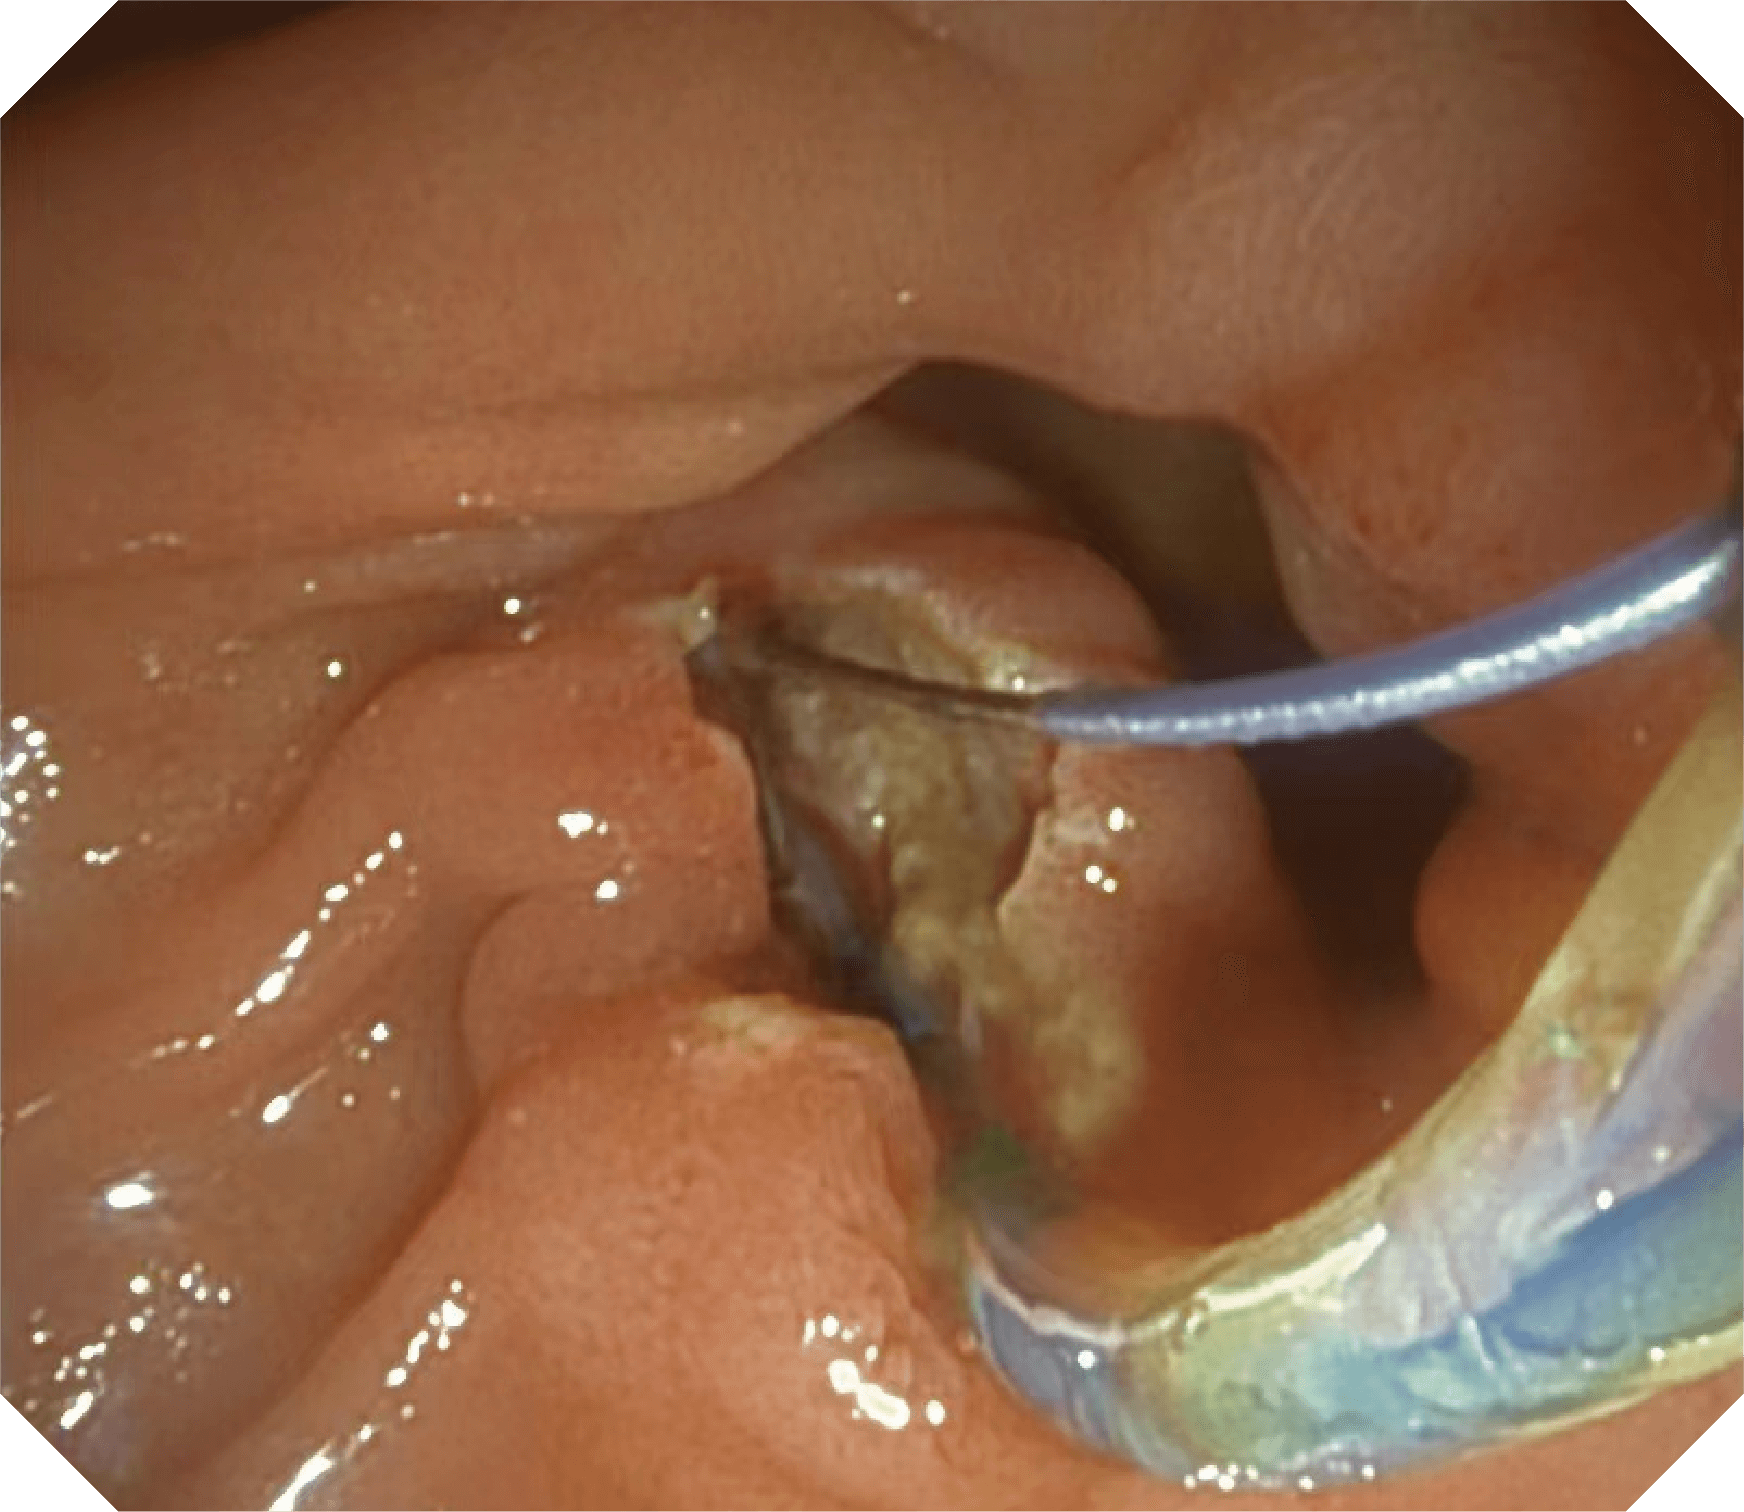

导丝机械锁紧功能

V槽设计提升导丝控制

优异的手术器械抬举性